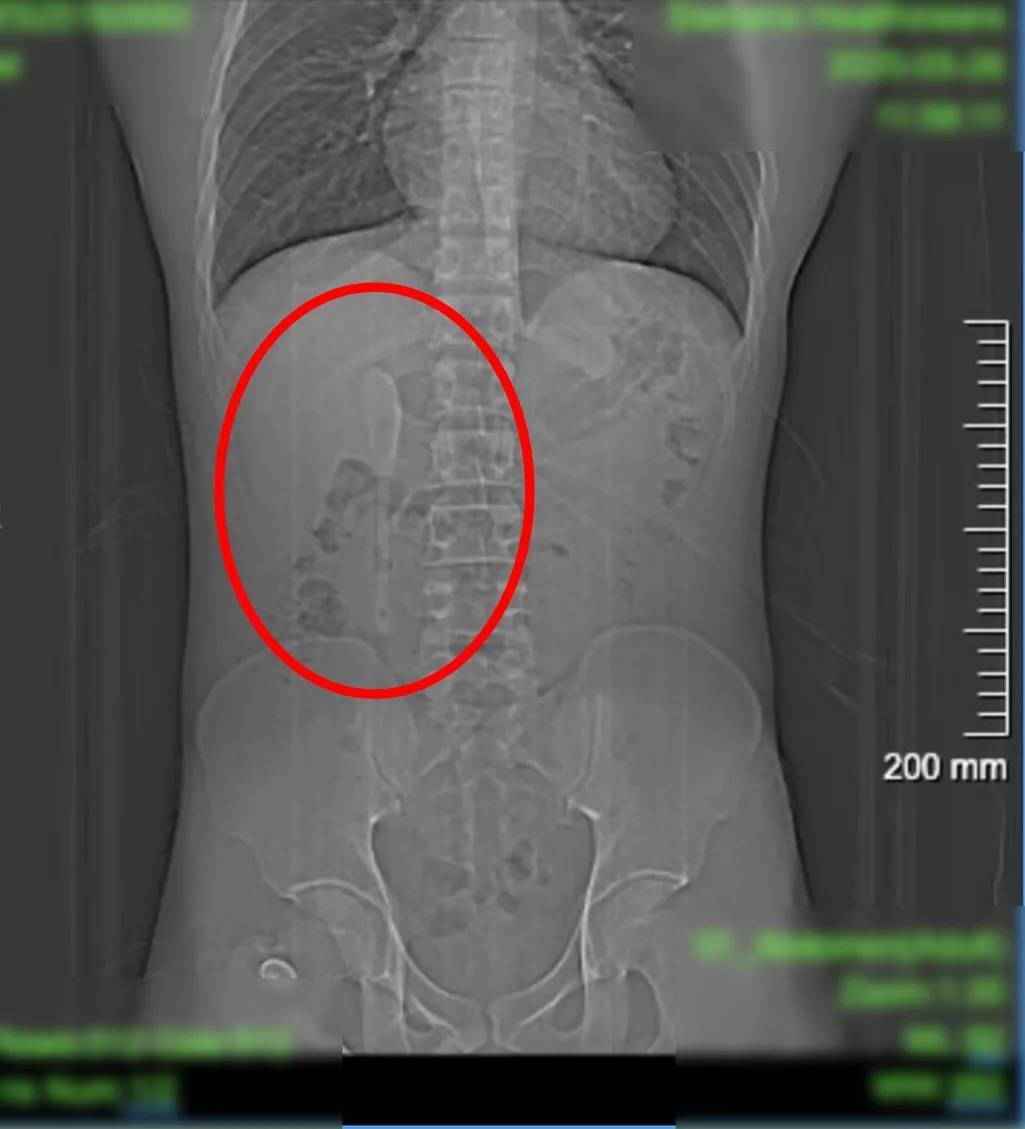

29岁的男子小言,近期因外卖吃出塑料异物,前往复旦大学附属中山医院急诊检查。谁知塑料没找到,竟意外发现腹中躺着一支近15厘米长的咖啡勺!

CT显示这支近15厘米长勺状物体,严丝合缝地横亘于十二指肠球部与降部交界的生理狭窄处,稍有不慎即可能刺穿肠壁,引发腹膜炎或大出血。更离奇的是,身为严格自律的健身人士,小言对此毫无记忆。

这支被遗忘的勺子,历经6个月胃肠蠕动,最终精准卡进十二指肠球部与降部交界处。此处腔隙狭窄且肠壁极为菲薄,异物极易嵌顿,稍有不慎容易造成穿孔。中山医院内镜中心主任周平红教授解释:“勺子陶瓷质地光滑细长,十二指肠球降交界又是人体上消化道的生理狭窄处,内镜下取出难度极大。若失败,只能开腹手术。”

6月18日下午,小言被推进了内镜手术室。虽然团队对手术难度有所预判,但内镜画面仍让团队倒吸凉气——勺子的“头”卡在十二指肠球部,而它的“长柄”则一路延伸下去,拐了个弯卡在了更深的十二指肠降部与水平部交界处。勺子表面太光滑,又长又硬,卡的角度刁钻,好不容易圈套器圈住了柄部,一用力,就从光滑的勺面脱了出来……套不住,根本套不住!圈套器反复滑脱,异物钳难以抓牢光滑勺面。